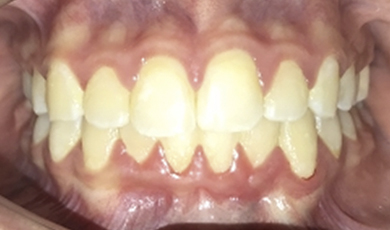

Finalização do tratamento

Após dois anos de acompanhamento o caso foi finalizado, conforme ilustram as imagens abaixo.